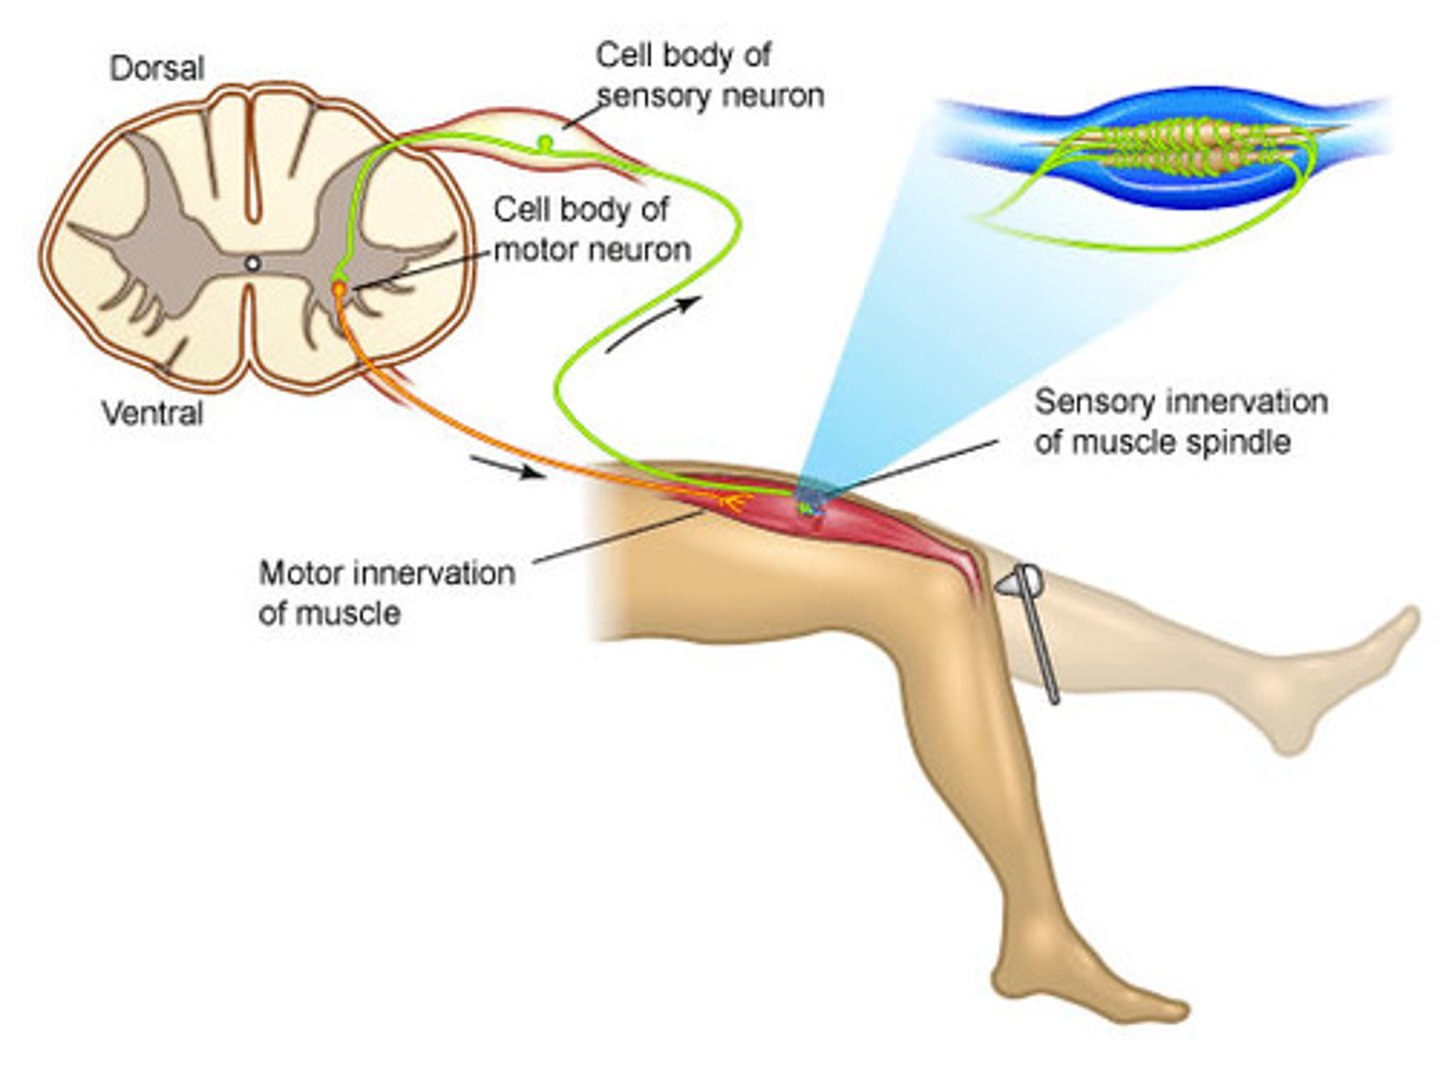

Step 1 of a simple reflex arc

Activation of a receptor by stimulus

Ex: Lean on tack, stimulates pain receptors

Step 2 of a simple reflex arc

Activation of a sensory neuron

Graded potential turns into an action potential in a sensory neuron

Step 3 of a simple reflex arc

Information processing in the CNS

Sensory neuron

→ excitatory postsynaptic potentials (EPSP) at interneuron

Step 4 of a simple reflex arc

Activation of motor neuron

Interneuron stimulates motor neurons

Collaterals from interneuron may send pain sensations to other areas in CNS

Step 5 of a simple reflex arc

Response of a peripheral effector

Ex: Skeletal muscle contraction to pull away from the tack

monosynaptic reflex

Single synapse—simplest reflex arc